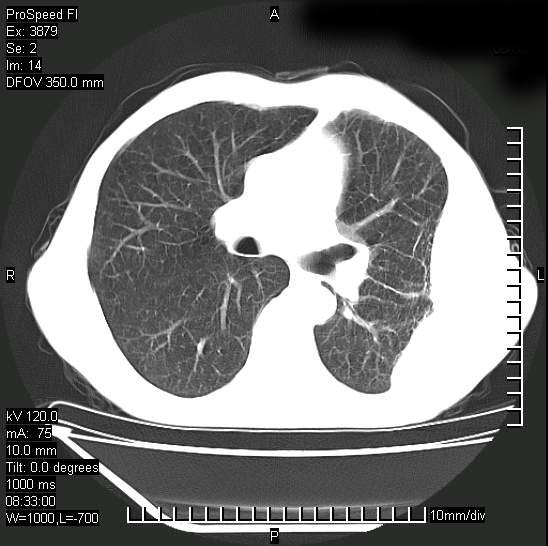

以下是引用37度在2008-6-6 11:20:00的发言:[br]1.包裹性积液,多考虑结核性;[br]2.穿刺术后改变。

以下是引用312nanyang在2008-6-6 15:12:00的发言:[br]基本支持楼主意见[br]疑问?左下肺支气管旁的软组织(16层)密度怎么解释?淋巴结还是斜裂胸膜增厚所致?能否增强进一步检查